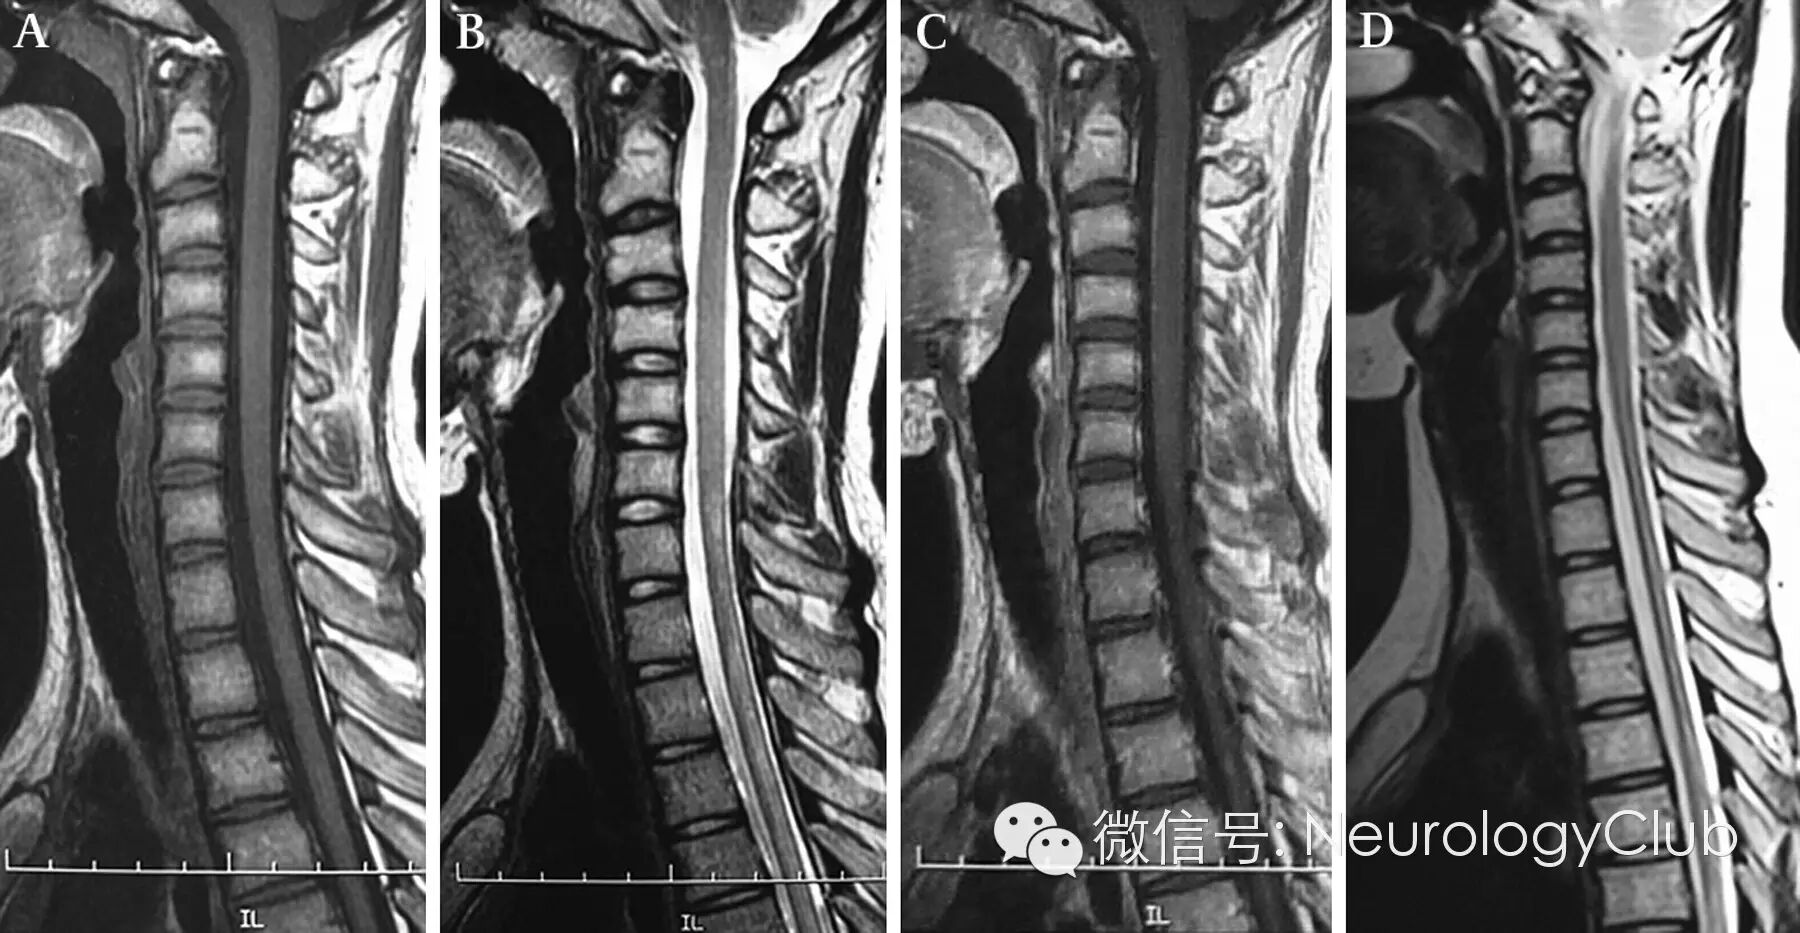

(一位16岁中国女孩,确诊为VKHS。A-B:可见C6椎体水平以下脊髓异常信号;C-D:随访2.5年后可见C6-T4椎体脊髓萎缩)